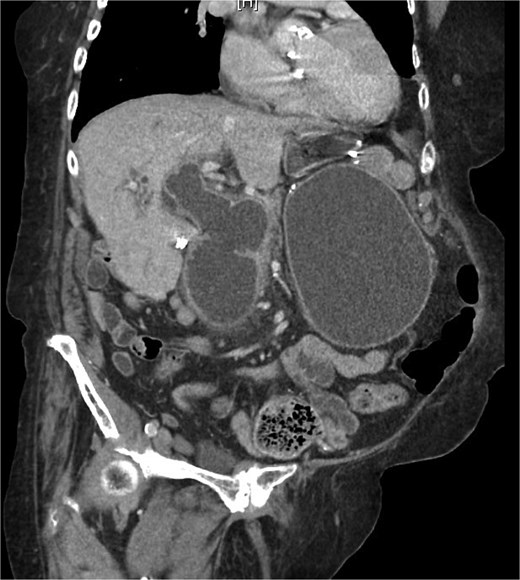

On examination, she was afebrile and hemodynamically stable. Her abdomen was mildly distended with epigastric tenderness and firmness. Laboratory workup revealed moderate leukocytosis (13.3 × 109/l), elevated lipase (288 U/l), and normal total bilirubin (0.8 mg/dl). Contrast-enhanced computed tomography (CT) demonstrated distention of the remnant stomach, duodenum (biliopancreatic limb), CBD, and intrahepatic ducts. A 9.0 × 3.4 cm heterogeneous mass was visualized in the duodenum, consistent with an obstructing gallstone (Figs 1–3).

CT demonstrating gallstone within the common bile duct 1 month prior to this admission.